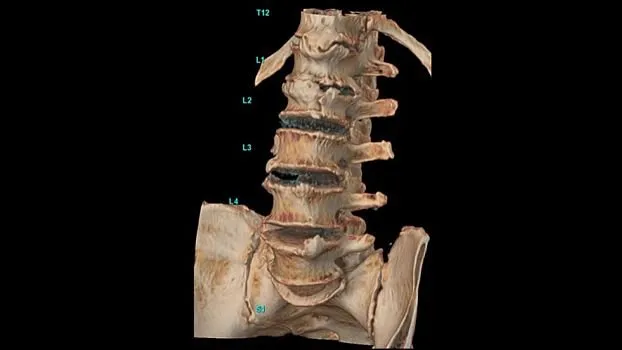

Клинические изображения

Апертура гентри

В Revolution Ascend сочетаются новая конструкция гентри диаметром 75 см и более низкое расположение стола, что позволяет увеличить площадь внутри туннеля, в пределах которой располагается пациент, на 22% по сравнению со сканерами GE HealthCare предыдущего поколения. Таким образом, пациенты чувствуют себя более комфортно во время КТ-исследований. Благодаря новой конструкции гентри, Revolution Ascend – КТ с самой большой апертурой среди систем с короткой геометрией¹. Это означает, что вы сможете проводить КТ пациентам крупного телосложения, а также пациентам с травмами, которые испытывали бы дискомфорт и не смогли бы свободно двигаться, если бы сканирование проходило в гентри меньшего размера.